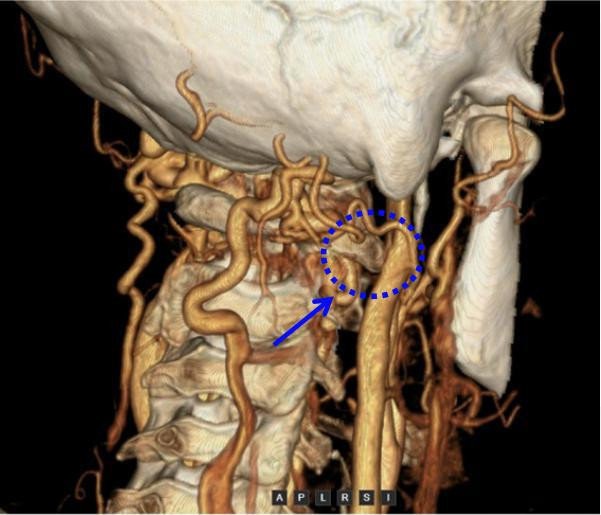

该院神经外科丁锐副主任医生接诊后,对周女士进行了详备的体魄查验与病史掂量,结合其诊疗资历,高度怀疑其脑鸣与头颈静脉回流报复关系。为明确诊断,团队第一时辰为其安排头颈部CT血管成像(CTA+CTV)查验。查验效果了了透露,周女士右侧颈内静脉J3段存在明确受压气象,回去拢椎静脉丛相等扩展——这为脑内相等声响的产生提供了明确的剖解学依据,也为后续诊疗指明了场所。

CTA查验教导右侧寰椎横突压迫颈内静脉(蓝色箭头所示压迫位置)

过程详备的术前沟通、多学科诊断,团队最终明确诊断周女士为“脑鸣详细征”,其根底病因是颈内静脉受到外源性骨性压迫,尤以寰椎横突骨质压迫最为权臣。